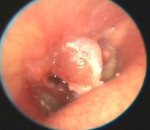

• Отоскопия. При объективном осмотре отоларинголог определяет наличие стойкой перфорации барабанной перепонки в периферической или центральной части, через которое происходит выделение гнойно-геморрагических патологических масс. После эвакуации последних в некоторых случаях в просвете дефекта выявляется образование красного или розового цвета.

• Отоэндоскопия. Осмотр барабанной полости при помощи эндоскопа дает возможность визуализировать структуру полипа. Определяется округлое, несколько подвижное образование с широкой основой или на ножке мягкой или уплотненной консистенции. Обнаруживается наличие ретракционных карманов барабанной перепонки, тимпаносклероз и тимпанофиброз, холестеатомный процесс, повреждения слуховых косточек и нарушения проходимости слуховой трубы.